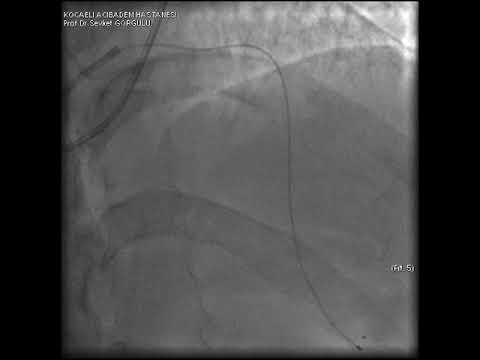

Microcatheter Tip Fracture During LAD CTO PCI A Complication Video 8